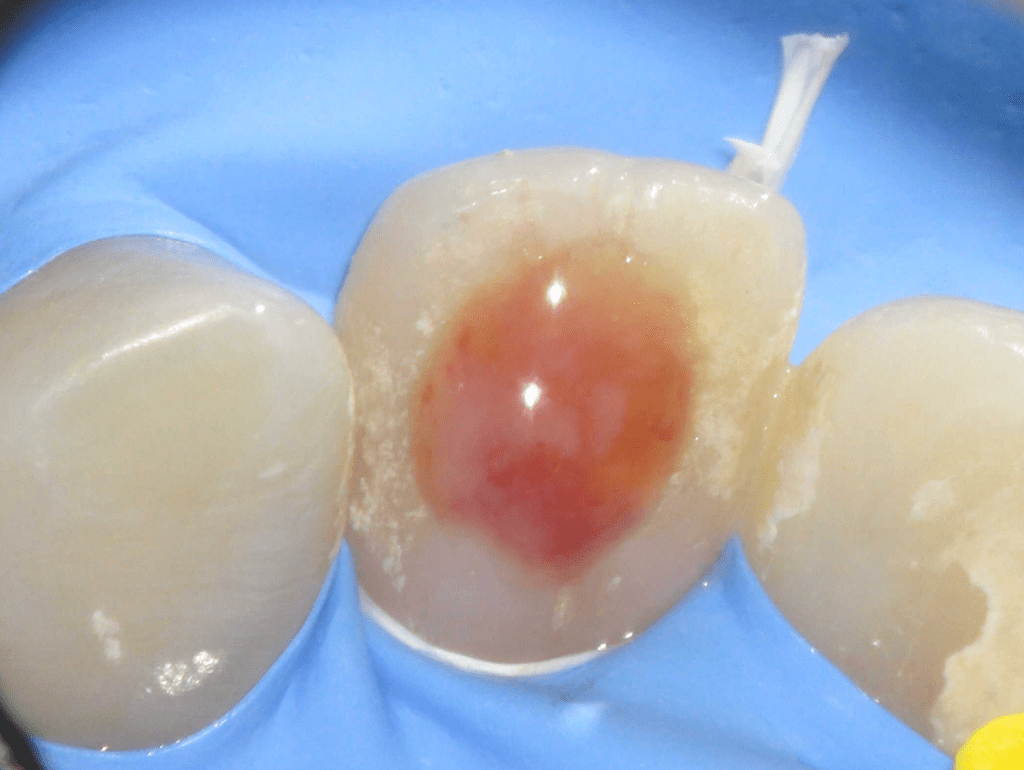

Fractura con exposición pulgar

Reconstrucción con recubrimiento pulgar indirecto